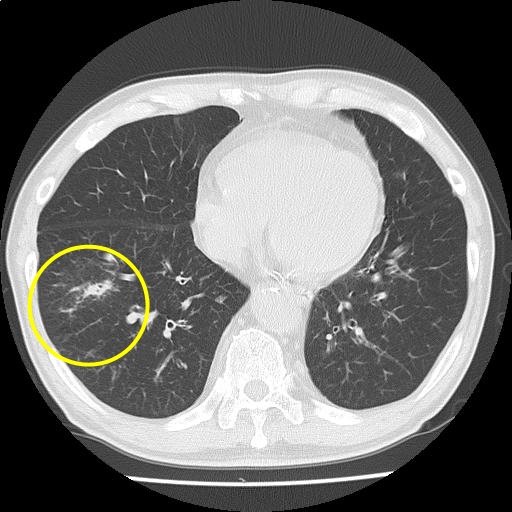

【画像診断検査結果】

(Findings)

肺野に気腫性変化を認める。

気管支壁肥厚はやや増悪。右肺優位に粒状影およびすりガラス影〜コンソリデーションの出現を認め、気管支肺炎を疑うが、 右下葉に一部腫瘤様にみえる所見あり、経過観察を要する。

縦隔リンパ節腫大を認めるが、炎症性反応と考える。

胸水は認めない。

(Impression)

s/o 気管支肺炎

CT画像3

(43/221)